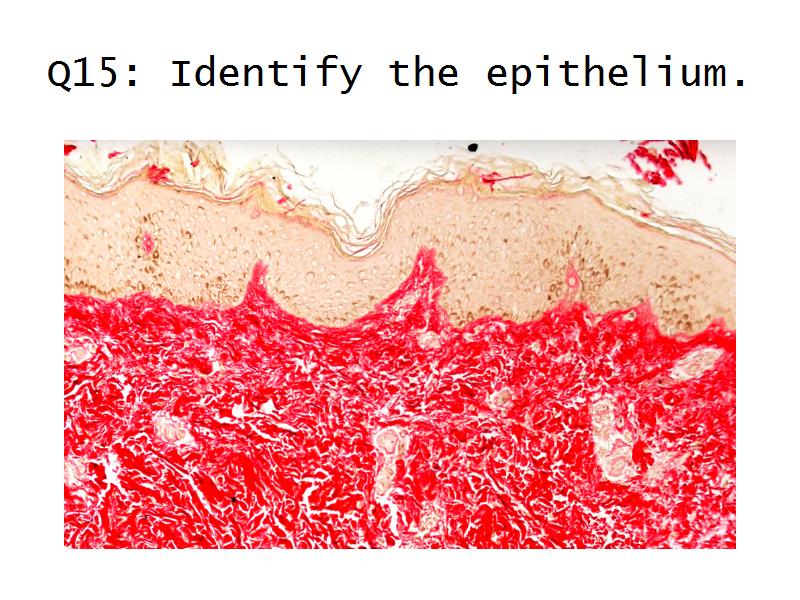

Q13: Name 1 epithelium for each.

Q13: Name 1 epithelium for each.

- Kidney = cuboidal, squamous

- Liver = squamous, cuboidal